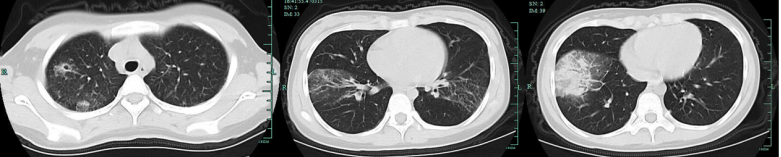

鼻病毒肺炎的影像学表现为双肺有多个模糊的斑片状磨玻璃影(图4箭头),小叶间隔增厚(图4箭头)。也有文献报道的鼻病毒肺炎的胸片显示双侧磨玻璃影和实变(图5a),胸部CT显示双侧磨玻璃影和小叶中心结节(图5b、c)

图片

图4  鼻病毒肺炎影像学表现(一)

图源:Radiographics, 2018, 38(3):719-739

图5  鼻病毒肺炎影像学表现(二)

图源:Respir Med Case Rep, 2019, 28:100910.